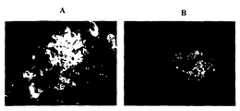

도 1: 베타-아밀로이드에 대한 항체. A: 인간 항체. B: 인간 베타-아밀로이드에 대한 공지된 항체로 염색된 대조군. 임상적으로 특이적으로 안정한 알츠하이머병 환자는 베타-아밀로이드 플라그 (plaque)에 대한 항체를 함유한다. 병리학적으로 확인된 알츠하이머병 환자로부터 수득한 뇌 단편의 임상적으로 특이적으로 안정한 환자로부터의 항체로의 면역조직화학적 염색은 인간 베타-아밀로이드에 대한 공지된 항체에 의해 확인된 베타-아밀로이드 플라그에 결합하는 항체를 나타낸다.